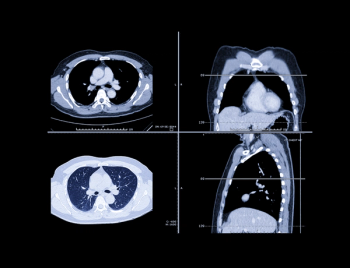

In the newly released Lung-RADS 2022 classification system for computed tomography (CT) lung cancer screening, the American College of Radiology (ACR) has noted a variety of updates including new classification criteria for atypical pulmonary cysts and airway nodules, time intervals for nodule growth and a new stepped management approach for Lung-RADS categories 3 and 4A.